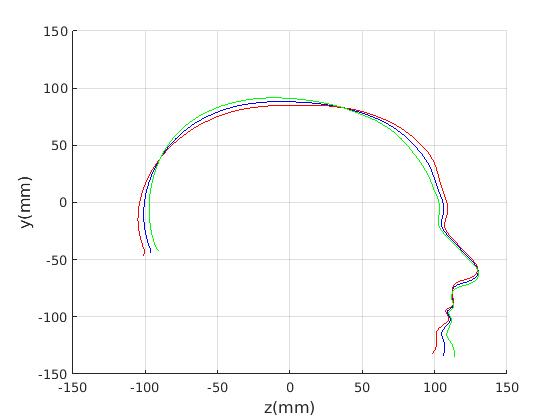

Figure 16 shows examples of the robust ellipse fit for four head profiles. The centre of the ellipse is used in a pose normalisation procedure where the ellipse centre is used as the origin of the profile and the angle from the ellipse centre to the nasion is fixed at -10 degrees. We call this Ellipse Centre - Nasion (ECN) pose normalisation and later compare this to GPA. The major and minor axes of the extracted ellipses are plotted as red and green lines respectively in Fig. 16.

|

Figure 17 shows all 100 profiles overlaid with the same alignment scheme. The median value of major ellipse axis and the ellipse centre-nasion angle differ by 3.6 degrees, so that when the nasion angle is fixed at -10 degrees, the median ellipse angle is -6.4 degrees (cf. -7.4 degrees with manual landmarking of the nasion). We noted regularity in the orientation of the fitted ellipse as is indicated by the clustering of the major (red) and minor (green) axes in Fig. 17 and the histogram of ellipse orientations in Fig. 18. For most people, the major axis of the ellipse is closely aligned with the y-axis (upright), and titled slightly forwards. A minority of heads (9%) in the training sample have their major ellipse axes closer to the vertical (these relatively tall and short heads are known as brachycephalic.) Ellipse axis clustering (relative to the fixed ellipse centre-nasion line) does not appear to be sharply defined. This is because many crania are close to circular in cross-section, making the orientation of these angles sensitive to small changes in shape from one person to the next. Note also the variation at the back of the head due to a variety of hair styles, some of which protrude from under the cap. We limit the region over which we model the cranial shape in order to crop this unwanted data out.